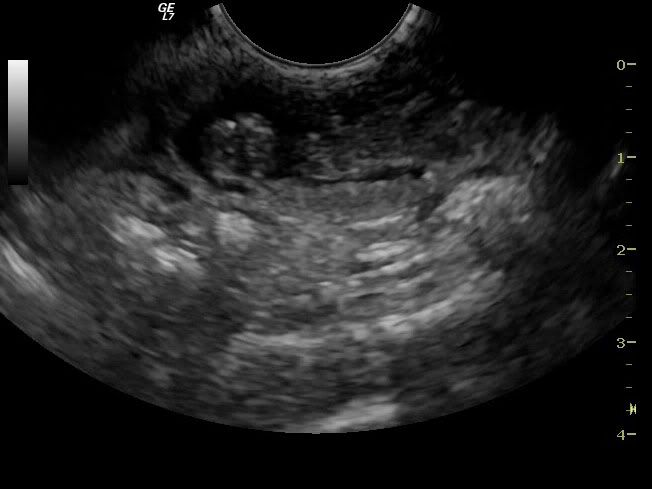

Og så nok det bedste screenshot jeg kunen tage, jeg synes den er ret tydelig :D Den ligger med ryggen til

med streger